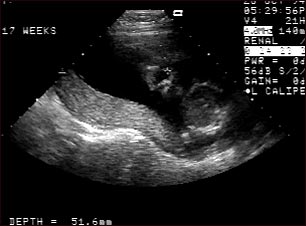

Ultrasonido normal , placenta relajada

Ultrasonido normal a las 19 semanas de gestación que muestra dos características interesantes. En primer plano, en el centro de la pantalla, se puede observar la placenta siguiendo la curvatura del útero. Al fondo y a la derecha, en el lugar que señala la cruz, se aprecia el rostro con todas las características faciales.